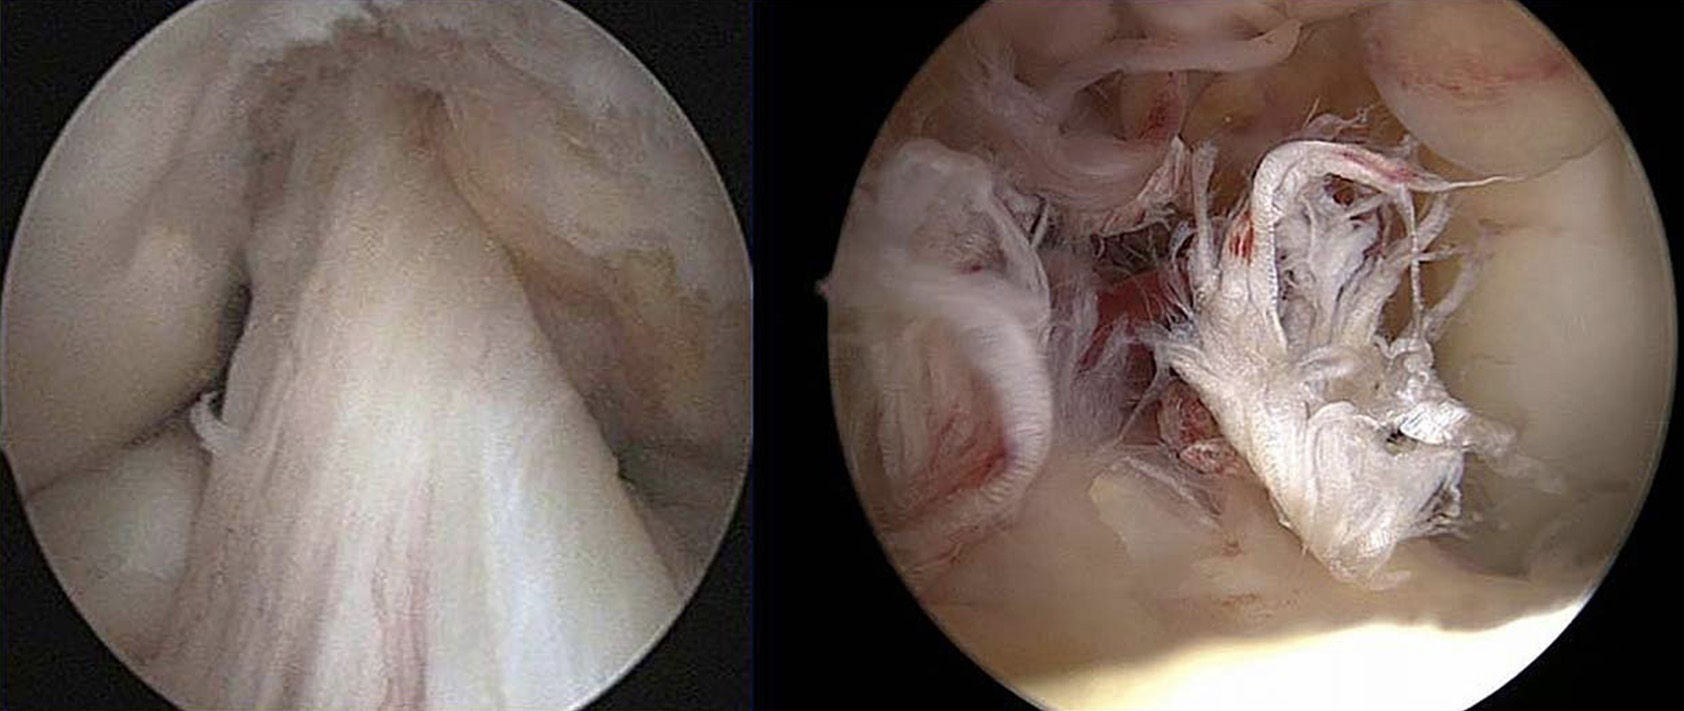

LCA intacto; rotura do LCA

Figura 4 – Imagem da esquerda evidencia LCA intacto; Imagem da direita, rotura do LCA